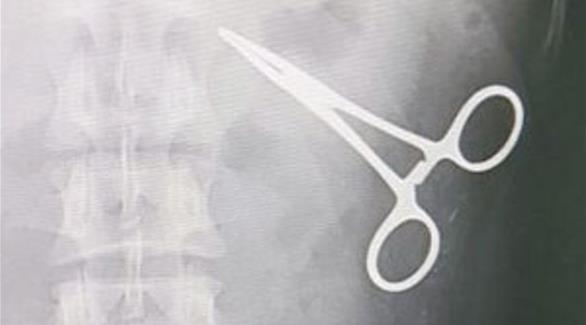

آلة كشف المعادن تعثر على مقص في بطن حاج